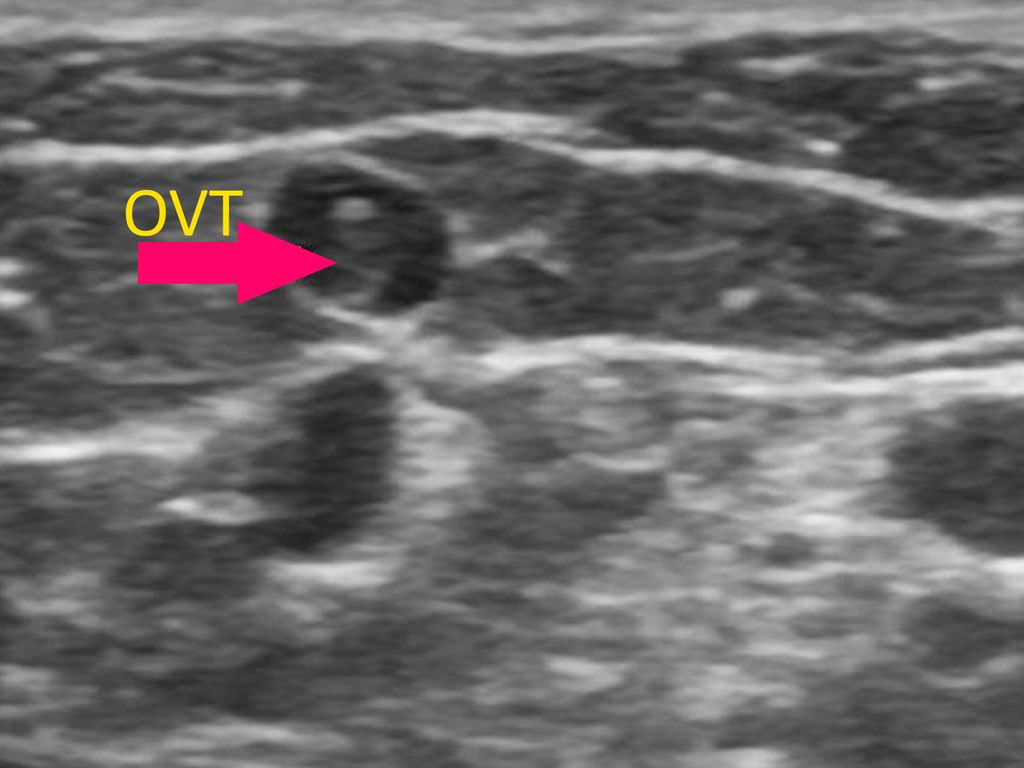

Die oberflächliche Venenthrombose (OVT) und Antikoagulation bei OVT

Allgemeinmedizin | Dermatologie | Innere Medizin | Kardiologie & Gefäßmedizin

| gültig bis April 2027

| 2

DFP Punkte

Allgemeinmedizin | Dermatologie | Innere Medizin | Kardiologie & Gefäßmedizin